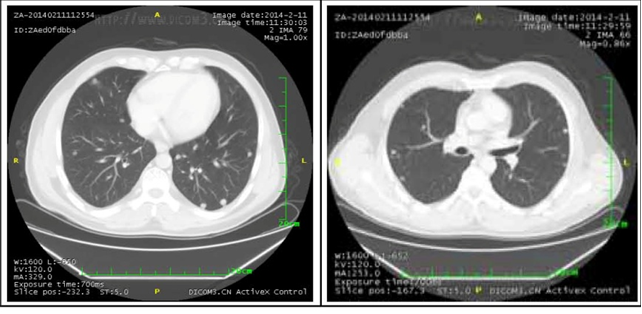

2. 肺部病灶治疗前后核磁对比:

肺部转移病灶在用药后2个月明显缩小,4个月后病灶基本消失。

治疗6个月

治疗16个月